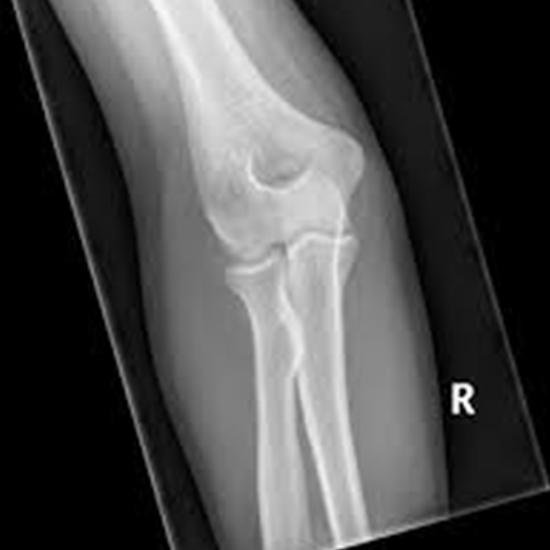

An X-ray of the elbow is used to see the bones of the elbow joint and the skin and muscles around it. The elbow area comprises the radius and ulna bones of the proximal forearm, the upper arm bone, and the elbow joint.